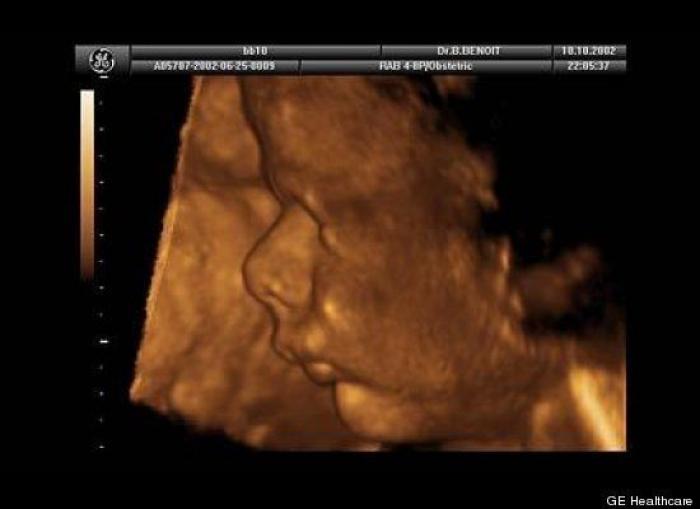

En esta galería puedes ver en fotos como es el desarrollo de un feto de semana en semana:

Desarrollo del feto, en fotos